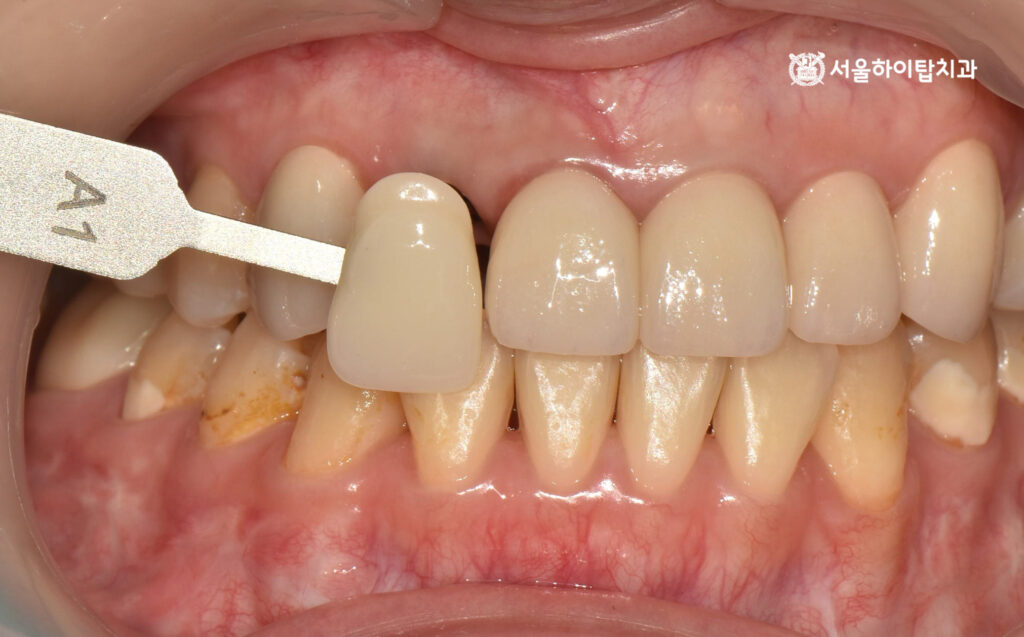

스캔바디 체결 및 쉐이트 체크

골유착이 충분히 이루어진 뒤에는 최종 보철 제작을 위해 스캔을 진행하게 됩니다.

이를 위해 스캔바디를 임플란트에 체결하여,

구강 내 스캐너로 임플란트의 위치, 각도, 깊이를 정확히 디지털로 기록합니다.

백운역 치과 에서는 이 과정을 통해 임플란트와 보철물의 정확한 맞춤이 가능하며,

이후 쉐이드 체크와 디자인을 통해 자연스러운 색상과 형태를 구현할 수 있습니다.

최종 보철 – 지르코니아 크라운 장착

앞서 진행한 쉐이드 체크를 통해 주변 자연치와 조화롭게 어울리는 색상을 선택되었으며,

이 데이터를 바탕으로 최종 지르코니아 크라운을 제작하여 장착한 모습입니다.